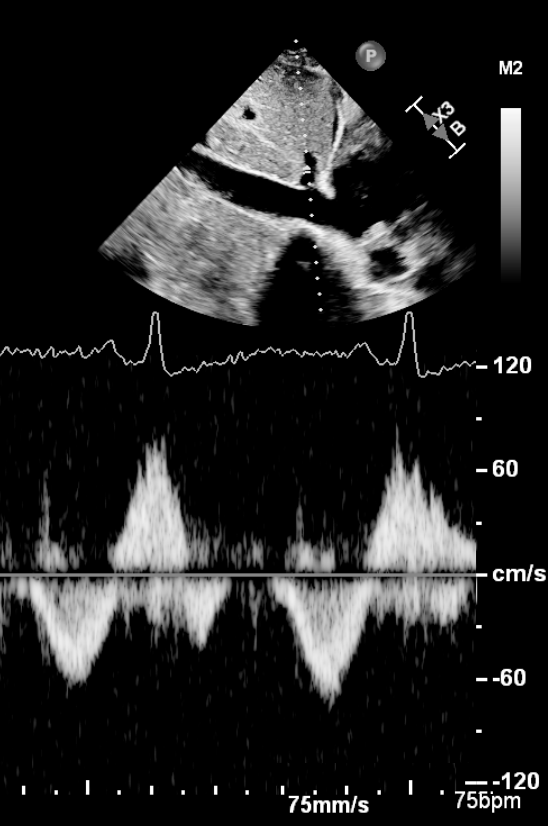

Very excited about publication by Elsevier of my textbook “High Quality Transesophageal Echocardiography” teaching details on how to do the procedure, and tips for an effective, optimized examination. #HighQualityTEE #MindfulEcho #echofirst #echotwitter